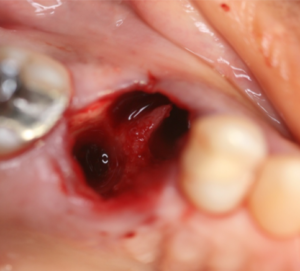

Vista oclusal do elemento16 pós-exodontia. Notar que a tábua vestibular foi reabsorvida.